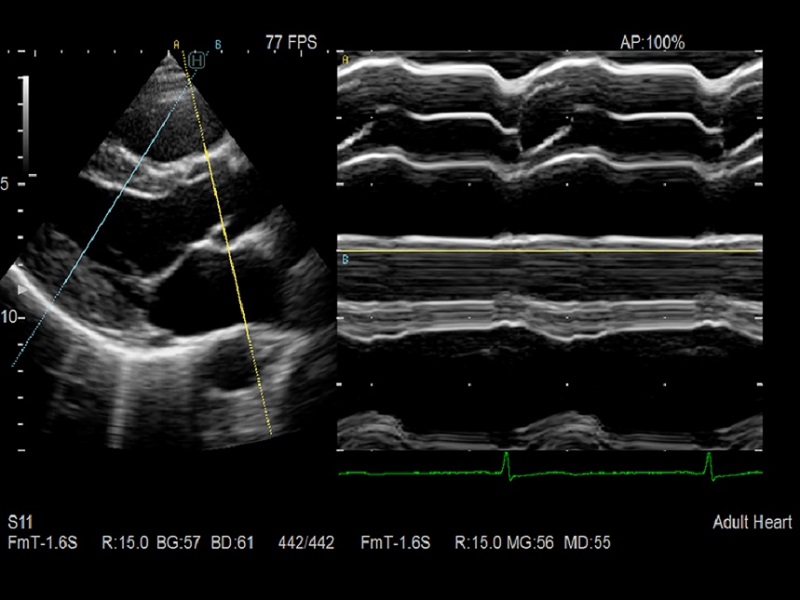

Dormed Hellas AR65 – Cardio CF Dormed Hellas AR65 – Cardio M-mode

Automatic tools for vascular and cardiac

2D Tissue Tracking (2DTT)

- Speckle tracking technique that quantifies the movement of the entire left ventricle or the local movement of the myocardium resulting in dynamic analysis of myocardium.

| Cardiac Functions | 2D Tissue Tracking (2DTT), ECG module, FAM (Free Angular M-mode), Myocardial Thickness (Wall Thickness), Strain Rate, Stress Echo, Stress Echo Analysis, TDI Analysis, Tissue Doppler Imaging (TDI), Transit Time of Vessel Flow (TVF) |